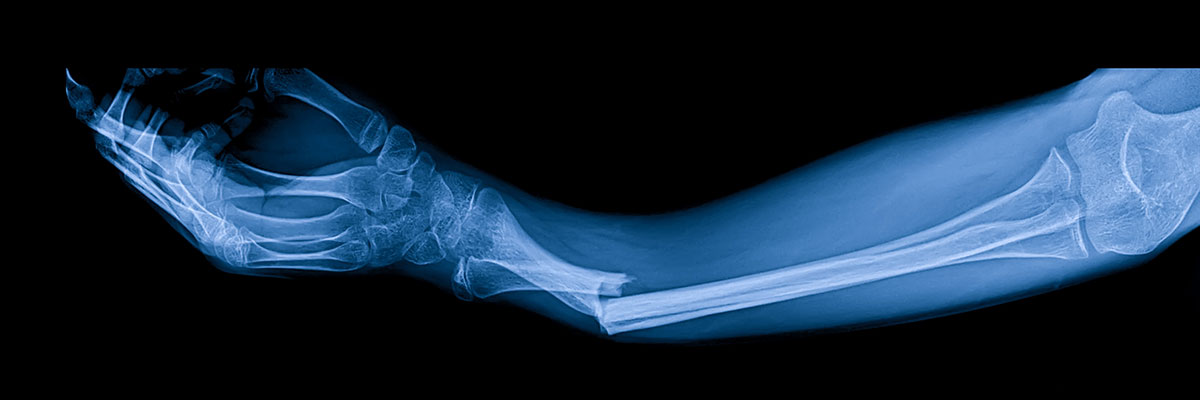

외상골절센터는 갑작스런 사고, 낙상 등 위급한 상황으로 인해 뼈가 부러지거나 금이 간 골절 환자 및 외상 환자에 대한 즉각적이고 전문적인 응급 진료 담당합니다. 또한 타과와의 유기적인 협진 체계를 갖추어 각 과별 임상 전문의와 함께 환자 개인별 증상에 맞는 보다 정확하고 정밀한 진료와 검사를 받을 수 있도록 합니다.

골절의 치료과정

• Step 01

응급처치

골절 발생 시 가장 중요한 것은 골절된 뼈가 움직이지 못하도록 고정시키는 것입니다.

보통 부목 등을 대어 간이 고정을 하는 경우가 많으나 처치 중 무리하게 움직이면 상태를 더욱 악화시킬 수 있기 때문에

구급차 등의 도움을 신속하게 요청하는 것이 중요합니다.

• Step 02

골절된 뼈의 치료

골절치료는 골절된 뼈를 정상적인 위치로 되돌리고, 그 기능 및 미관을 가능한 정상에 가깝도록 회복시켜

본래의 생활로 복귀시키는 데 있습니다. 골절은 환자의 연령, 전신상태, 손상정도, 손상부위 및 합병증의 유무에 따라

가벼운 처치만으로 치료할 수 있는 경우부터 관혈적 정복 및 금속 내 고정을 요하는 경우까지 여러 가지 치료방법이 있습니다.

• Step 03

재활

골유합이 되면 석고붕대나 석고부목 등의 외부 고정물을 제거하고, 관절운동을 시행함과 동시에 손상된 사지의 기능 회복을 위하여

물리치료를 병행하게 됩니다. 가장 중요한 것은 환자 스스로 능동적으로 운동을 해야 한다는 것이며, 관절 운동 시작 전에 온찜질과

부드러운 마사지 및 전기치료, 따뜻한 물에서의 목욕 등은 관절 운동을 촉진시킬 수 있습니다.